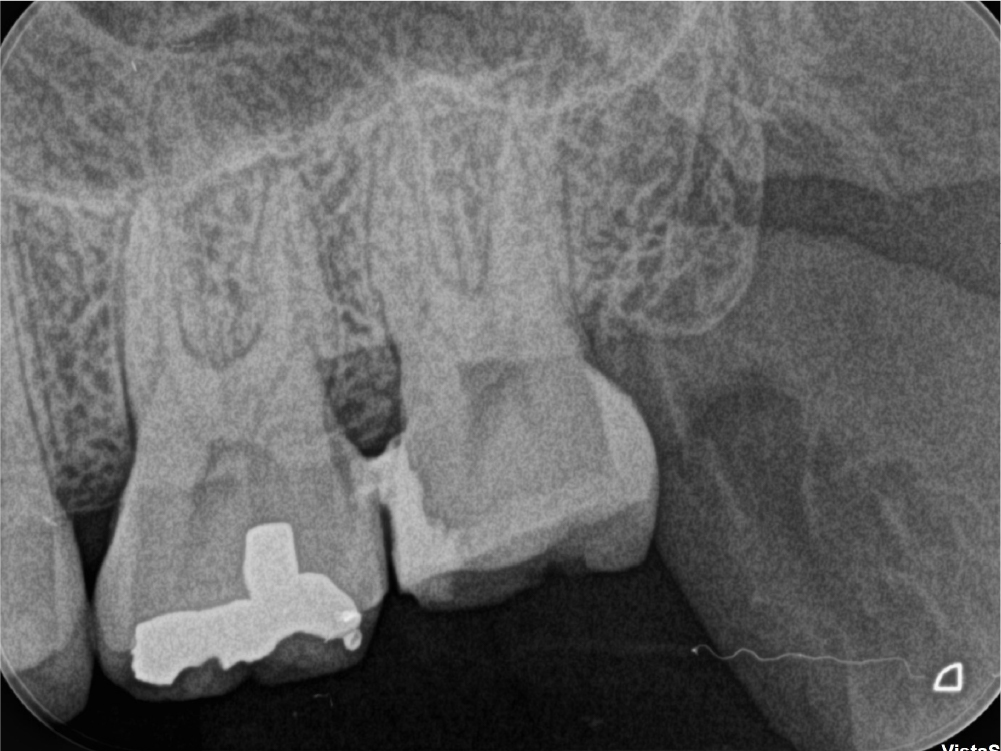

根管治療の症例

術前

術後1年

他院で行った過去の処置の影響で、歯の内部に穿孔(本来ない部位に穴が開く状態)が生じ、分岐部付近に根管充填材が迷入している状態でした。歯内療法の専門的な視点で穿孔部位を正確に特定し、迷入した充填材を除去。穿孔部を封鎖(封鎖処置)したうえで、根管治療を再度行い、経過観察で症状と所見の改善を確認しました。

年齢性別 10代・男性

主訴 腫れている

治療部位 左下6番

治療内容 穿孔部のガッタパーチャ除去 → 穿孔封鎖 → 再根管治療

治療回数 2回

リスク副作用 穿孔の位置や大きさによっては封鎖が難しく、治癒が得られない場合があります。術後に腫れや痛みが出ることがあり、経過観察が必要です。

担当医からのコメント

穿孔は、根管治療の中でも特に難易度が高いトラブルの一つです。診断が曖昧なまま進めると悪化することもありますが、歯内療法の専門医が状態を的確に見極め、封鎖を適切に行うことで、抜歯を回避できる可能性があります。